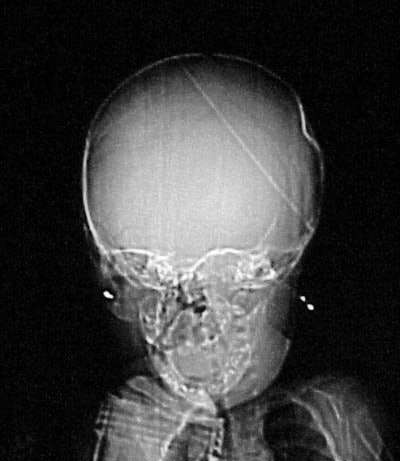

How about CT imaging for an in vitro trauma? Figure CT 5 is an axial image of a newborn child; there were no problems during the caesarian delivery. Two physicians and three nurses were present and the child was noted to have an indentation to the temporal region of the skull. Plain films were positive for a depressed skull fracture (Figure CT 6).

![]() |

| Figure CT 6 |

Three-dimensional reconstructed images in surface-shaded volume rendering show an obvious breech of the skull in the affected area (figures CT 7 and CT 8). Detectives matched the defect to a pair of the father’s cowboy boots. He was charged and convicted of beating his wife during the pregnancy.